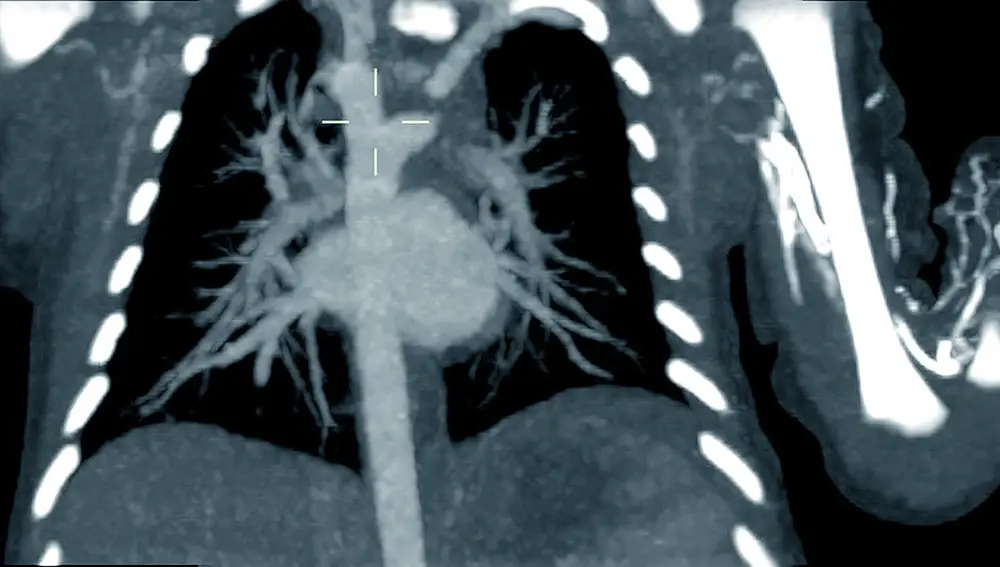

Esto fue lo que pasó con un bebé de dos días de vida al que se tuvo que realizar una tomografía computerizada (TC) de ultra baja radiación para confirmar la presencia de un doble arco aórtico, es decir, dos ramas de la aorta que rodean la tráquea y el esófago del bebé. La detección de este caso se realizó intraútero; sin embargo, una vez nacido, el pequeño fue sometido a esta prueba para tener una visión más precisa de la lesión que tenía para planificar una cirugía.

«Esta patología se da en recién nacidos que no sólo tienen un cayado aórtico, sino dos. En estos casos el cayado derecho suele ser el dominante», explica la doctora Ana Álvarez, del Servicio de Diagnóstico por la Imagen. «Estos bebés sufren un riesgo de estenosis de la vía aérea o digestiva y pudiendo presentar tos recurrente, neumonías de repetición y problemas para tragar que sería necesario corregir quirúrgicamente», continúa la experta.